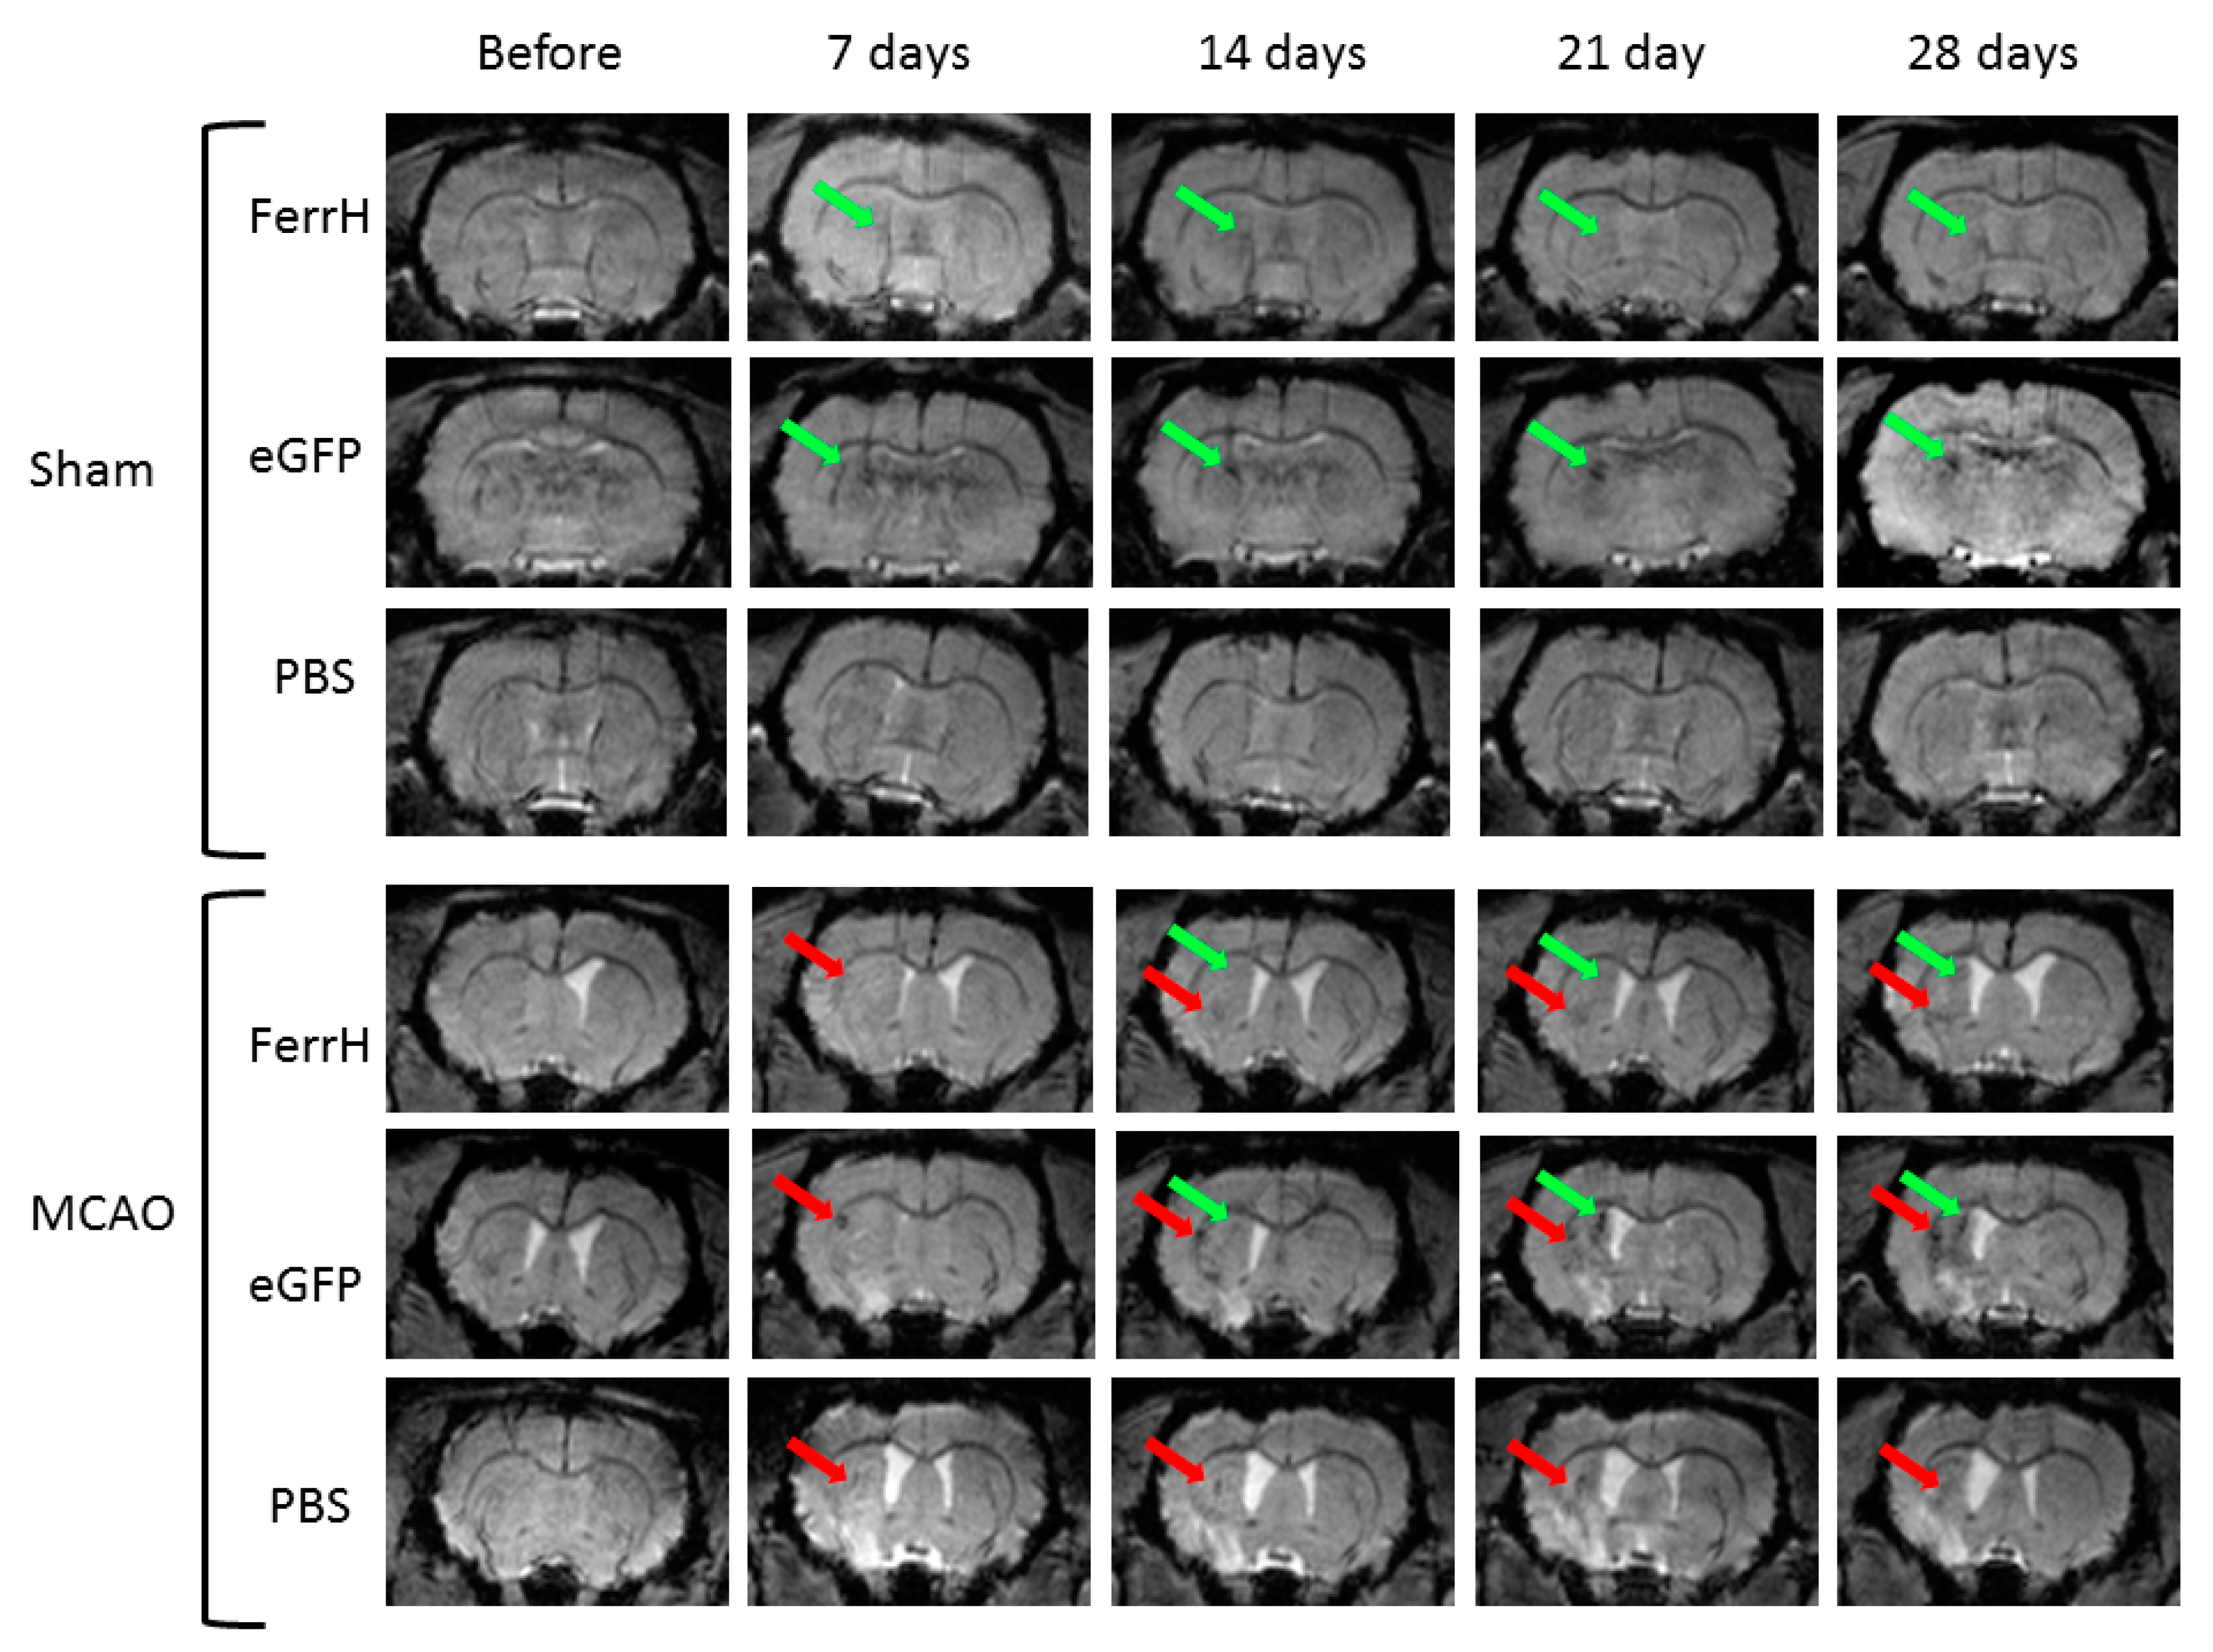

2.2. Injections of Both AAV-pDCX-FerrH and AAV-pDCX-eGFP Cause Signal Hypointensity on T2*-MGE Images in the Sham-Operated and Post-Ischemic Animals

2.3. T2* Signal Hypointensity Correlates with FerrH and eGFP Accumulation

- Results of our study showed that rat brain could be successfully infected with AAV-pDCX-FerrH and AAV-pDCX-eGFP viral vectors for expression of either ferritin or eGFP. Both vectors caused at about 20% decrease in signal hypointensity in the areas near the SVZ on T2*-weighted MRI at one month after intracranial injection of the viral constructs.

- The location of the signal hypointensity areas coincides with zones of ferritin and eGFP accumulation in immunohistochemical slides and zones of iron accumulation in Prussian blue staining a month after viral injection. RT-PCR data confirmed upregulated expression of the ferritin in the corpus callosum and caudoputamen in the left hemisphere of the rat brain on day 7 after intracerebral injected of the adenoviral vector construct.

- The main source of the signal hypointensity near SVZs in the AAV-pDCX-FerrH and AAV-pDCX-eGFP groups are mature neurons with a small percentage of young neurons.

- The main source of the signal hypointensity in the ischemic lesion area in AAV-pDCX-FerrH, AAV-pDCX-eGFP, and PBS-injected groups is macrophages.